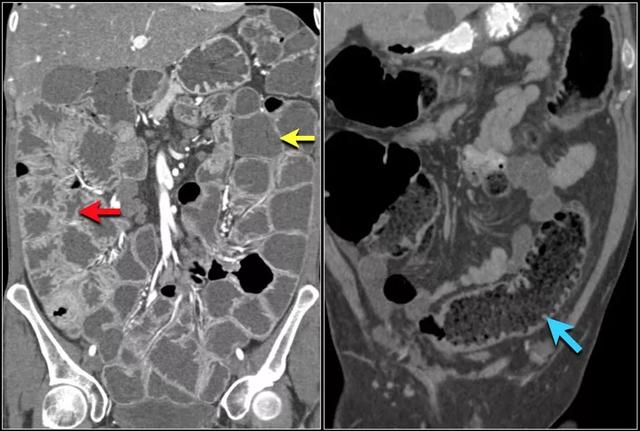

下图是一个闭袢性小肠梗阻。注意右上腹部壁增厚的小肠环组(黄色箭头)。

肠系膜水肿(红色箭头)表明静脉压因绞窄而增加。

静脉压的增加也会导致静脉充盈(下图黄色箭头),这也是个闭袢性肠梗阻的幌子,灰白色强化的肠环(红色箭头)。注意梗阻近端小肠的正常强化(绿色箭头)。